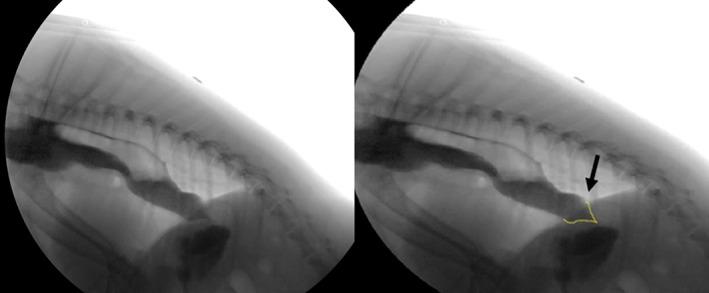

HYPOTHESIS/OBJECTIVES: To identify dogs with videofluoroscopic swallow study (VFSS) features of LES achalasia-like syndrome (LES-AS). We hypothesized that dogs with LES-AS could be distinguished from normal dogs using standardized VFSS criteria.

Retrospective study. One-hundred thirty dogs presented to the University of Missouri Veterinary Health Center (MU-VHC) between April 2015 and December 2017 for a free-feeding VFSS; 20 healthy dogs were included as controls. Swallow studies were evaluated for failure of the LES to relax during pharyngeal swallow (LES-AS). Affected dogs subsequently were evaluated using standardized criteria to identify metrics important for identifying and characterizing dogs with LES-AS.

Nineteen dogs with LES-AS were identified out of 130 VFSS. Megaesophagus was present in 14 of 19 (73.7%) dogs with LES-AS. A baseline esophageal fluid-line and "bird beak" were present in 68.4% (95% confidence interval [CI], 47.5%-89.3%) and 63.2% (95% CI, 41.5%-84.8%) of affected dogs, respectively. The esophagus was graded as acontractile (8/19), hypomotile (8/19), or hypermotile (3/19).

Dogs with LES-AS may successfully be identified by VFSS using a free-feeding protocol. These data are of critical clinical importance because a subpopulation of dogs with functional LES obstruction may be candidates for targeted intervention.

假设/目的:确定具有 LES 失弛缓症样综合征(LES-AS)的食管造影吞咽研究(VFSS)特征的犬。我们假设可以使用标准化的 VFSS 标准将具有 LES-AS 的犬与正常犬区分开来。

回顾性研究。2015 年 4 月至 2017 年 12 月,130 只犬在密苏里大学兽医学院就诊(MU-VHC)进行自由喂养 VFSS;20 只健康犬作为对照。吞咽研究评估 LES 在咽部吞咽期间是否无法放松(LES-AS)。受影响的犬随后使用标准化标准进行评估,以确定识别和表征 LES-AS 犬的重要指标。

在 130 次 VFSS 中确定了 19 只具有 LES-AS 的犬。19 只 LES-AS 犬中有 14 只(73.7%)患有巨食管。68.4%(95%置信区间[CI],47.5%-89.3%)和 63.2%(95% CI,41.5%-84.8%)的受影响犬存在基线食管液体线和“鸟嘴”。食管被分级为无收缩(8/19)、低动力(8/19)或高动力(3/19)。

LES-AS 犬可通过使用自由喂养方案的 VFSS 成功识别。这些数据具有重要的临床意义,因为功能性 LES 阻塞的犬亚群可能是靶向干预的候选者。